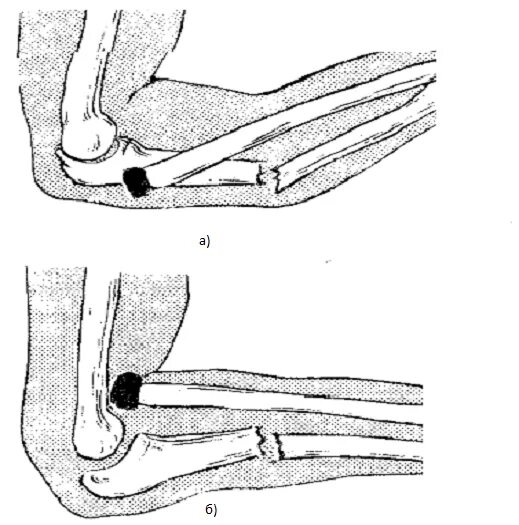

Перелом локтевой